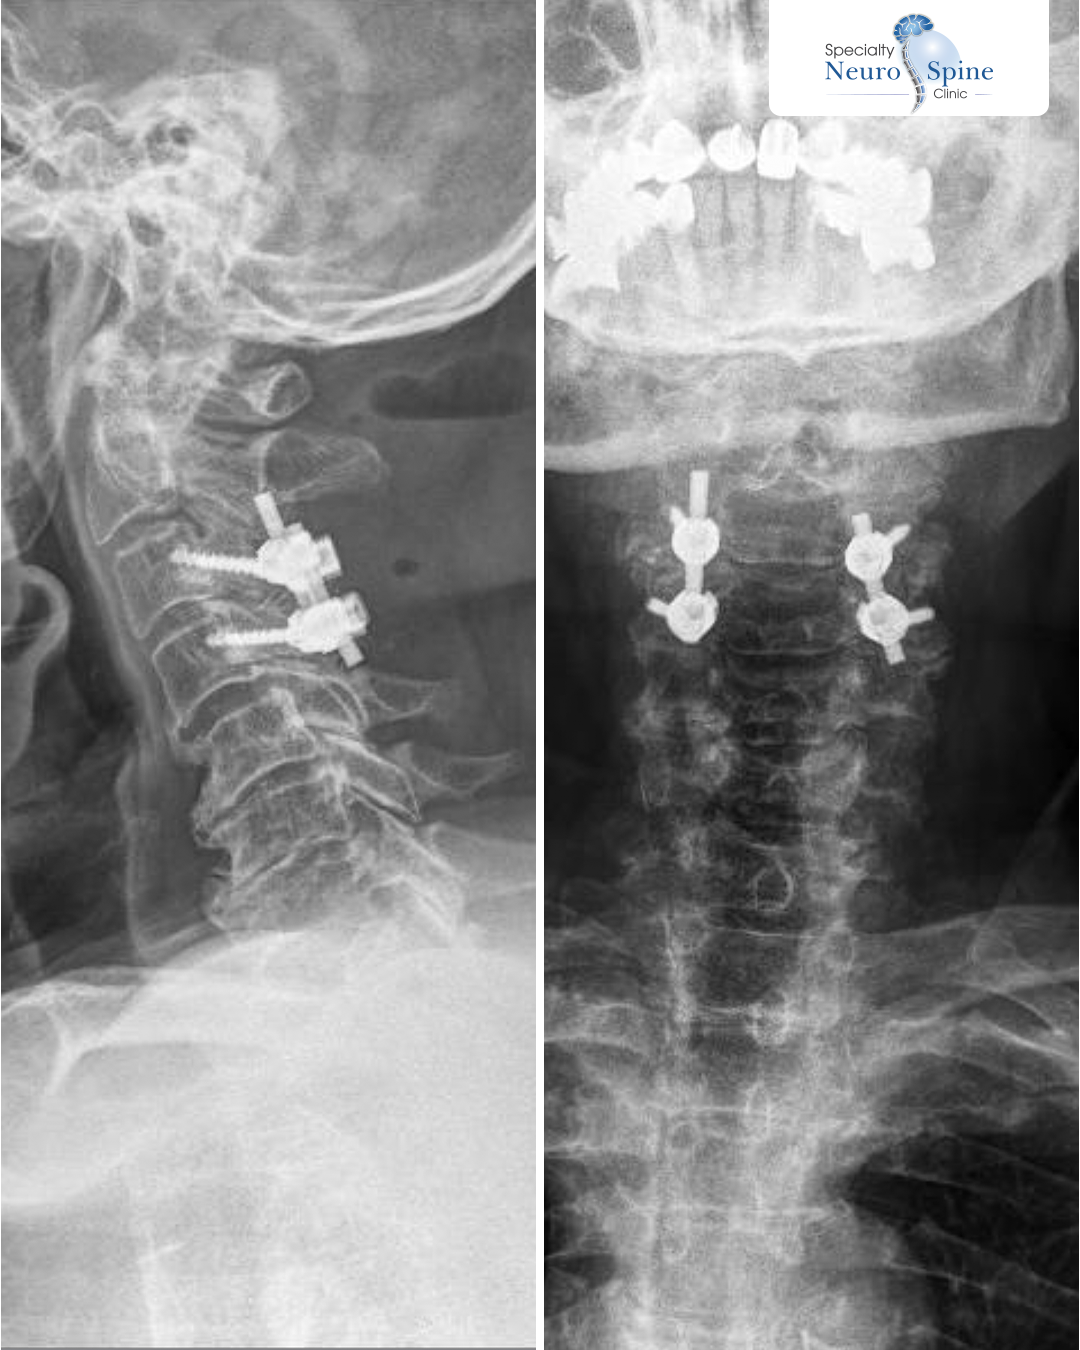

journalist Muneim Fakhouri’s Journey – Minimally Invasive Cervical Spine Fusion Procedure

We were pleased to welcome our esteemed patient, journalist Muneim Fakhouri, who underwent a minimally invasive cervical spine fusion procedure.

The patient was suffering from spinal canal stenosis, which led to reduced blood flow and neuropathy, resulting in impaired balance while walking and difficulty controlling limb movements.